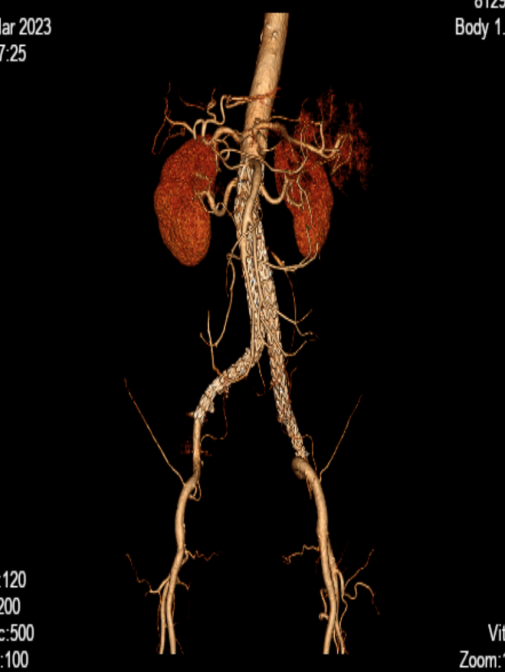

據(jù)了解,2月24日,患者李伯在進(jìn)行腦血管造影檢查時,意外發(fā)現(xiàn)了腹主動脈有巨大的動脈瘤及雙側(cè)髂動脈巨大動脈瘤。經(jīng)過測量,李伯腹主動脈夾層動脈瘤瘤體直徑約8.6cm,上下徑約11.6cm,瘤體較大且延伸至雙側(cè)髂動脈。

根據(jù)李伯腹部+盆腔CTA結(jié)果,神經(jīng)內(nèi)科介入團(tuán)隊與李伯的家屬進(jìn)行了充分溝通且經(jīng)家屬同意后決定為李伯進(jìn)行手術(shù)治療。術(shù)前,神經(jīng)內(nèi)科介入團(tuán)隊繪制了精確的評估草圖,充分做好手術(shù)預(yù)案。

術(shù)后CTA

術(shù)后,李伯再次造影提示支架貼合良好,且未發(fā)現(xiàn)內(nèi)漏、周圍臟器血管閉塞等并發(fā)癥。次日李伯就能下床活動,行走自如。目前,西電集團(tuán)醫(yī)院神經(jīng)內(nèi)科介入團(tuán)隊已成功為四名患者“拆除”腹腔“炸彈”。